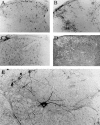

Involvement of viruses in human neurodegenerative diseases and the underlying pathologic mechanisms remain generally unclear. Human respiratory coronaviruses (HCoV) can infect neural cells, persist in human brain, and activate myelin-reactive T cells. As a means of understanding the human infection, we characterized in vivo the neurotropic and neuroinvasive properties of HCoV-OC43 through the development of an experimental animal model. Virus inoculation of 21-day postnatal C57BL/6 and BALB/c mice led to a generalized infection of the whole CNS, demonstrating HCoV-OC43 neuroinvasiveness and neurovirulence. This acute infection targeted neurons, which underwent vacuolation and degeneration while infected regions presented strong microglial reactivity and inflammatory reactions. Damage to the CNS was not immunologically mediated and microglial reactivity was instead a consequence of direct virus-mediated neuronal injury. Although this acute encephalitis appears generally similar to that induced by murine coronaviruses, an important difference rests in the prominent spongiform-like degeneration that could trigger neuropathology in surviving animals.